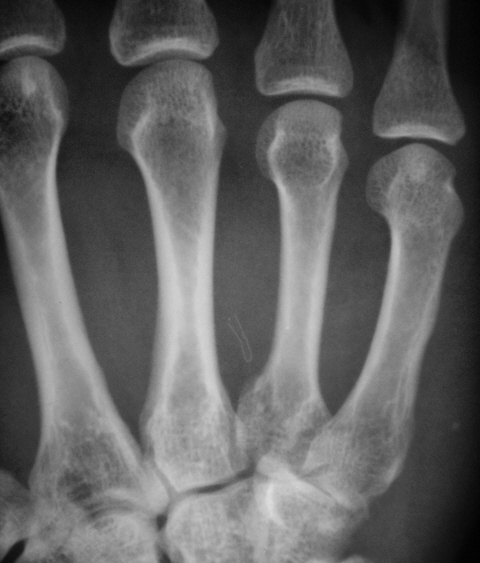

4 пястная перелом

4 пястная перелом 113 фотографий